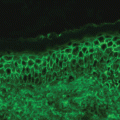

Conjugate Vaccines (Fig. 49.1) [1, 130]

Fig. 49.1

Antibody responses to polysaccharide antigens and polysaccharide–protein conjugates. (a) A polysaccharide antigen binds to an immunoglobulin M (IgM) receptor on the surface of a B cell in lymphoid tissues. Once B cells are activated, they produce and then secrete IgM antibody molecules. The individual Fab segments of the IgM molecule have only a moderate affinity, but because there are 10 such segments, an IgM molecule has a high avidity. (b) In contrast, some polysaccharide–protein conjugates are taken up by dendritic cells, which present peptides from the protein portion of the conjugate to type 2 helper T (Th2) cells. Other conjugate molecules bind to B cells that have IgM receptors specific for the carbohydrate moiety and will undergo endocytosis and be processed by the B cell; the resulting peptides will be expressed with major histocompatibility complex (MHC) class II molecules on the surface of the B cell

Many bacteria, including Neisseria meningitidis and Haemophilus species, have an outer capsule composed of polysaccharides that are species and type specific for particular strains of the bacterium. The goal of vaccination is to generate antibodies against the polysaccharide capsule of the bacteria since the most effective defense against these organisms is opsonization of the polysaccharide coat with antibody. However, children under 2 years of age do not mount a good response against capsular polysaccharide, which is a T-cell–independent antigen. An effective way to overcome this problem is to conjugate bacterial polysaccharide (chemically) to protein carriers, which offer peptides that can be recognized by antigen-specific T cells. Thus, a T-independent response is converted into a T-cell–dependent antipolysaccharide response [1, 39].